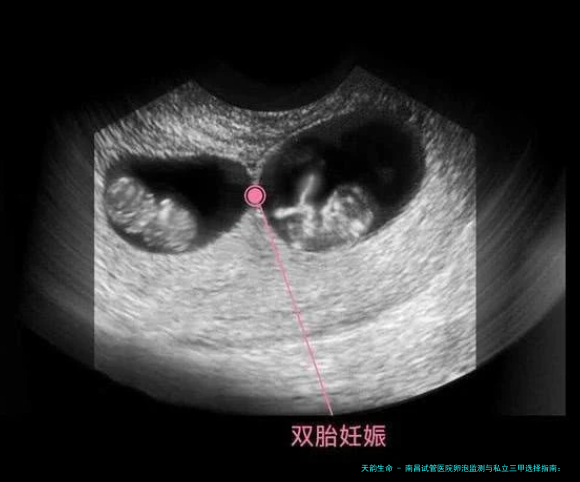

为什么卵泡监测在试管婴儿中如此关键?

卵泡监测是试管婴儿周期中的“眼睛”。通过连续的B超检查,医生可以清晰地观测卵泡的数目、大小和发展速度。这决计了几个重要节点:

一家医院在卵泡监测上的配备精度(如高清阴道B超)、医生经验(对图像的理解评价)以及监测频率的合理安排,都直接影响到周期的结局。